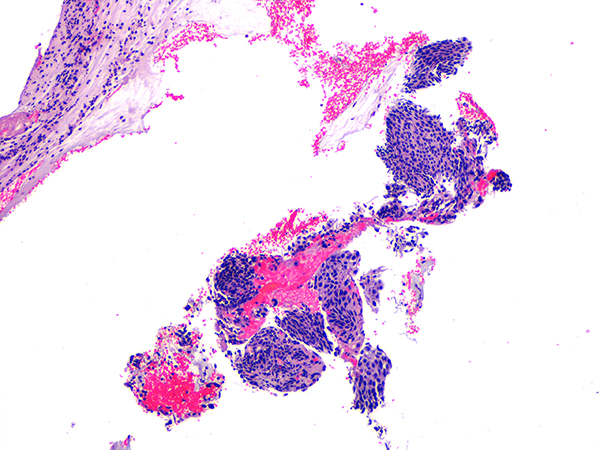

![]() Case 2

Soft Bx CIN 2 10x - Low Power |